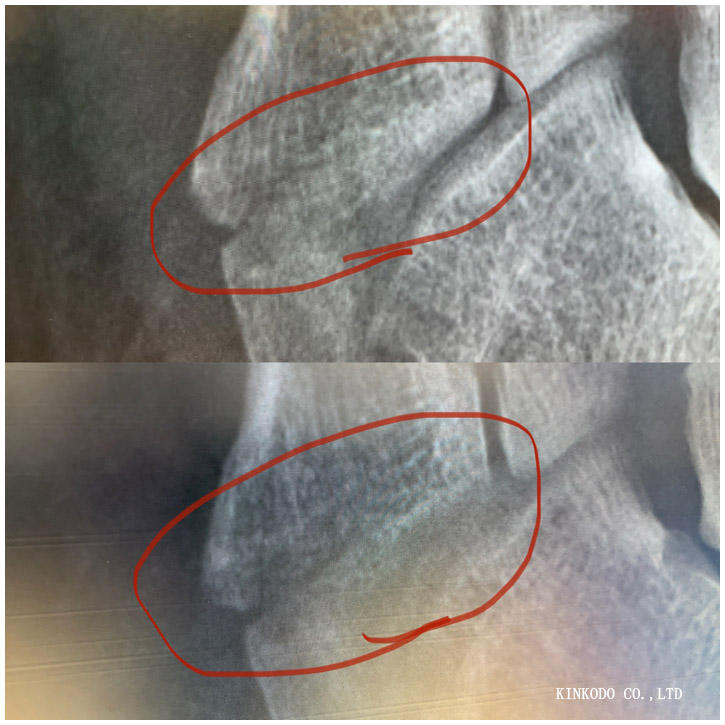

骨折してちょうど10週目。骨折した日を入れると71日目。

下が二週間前、そして上が今日。素人目にみてもくっついているように思うけど。